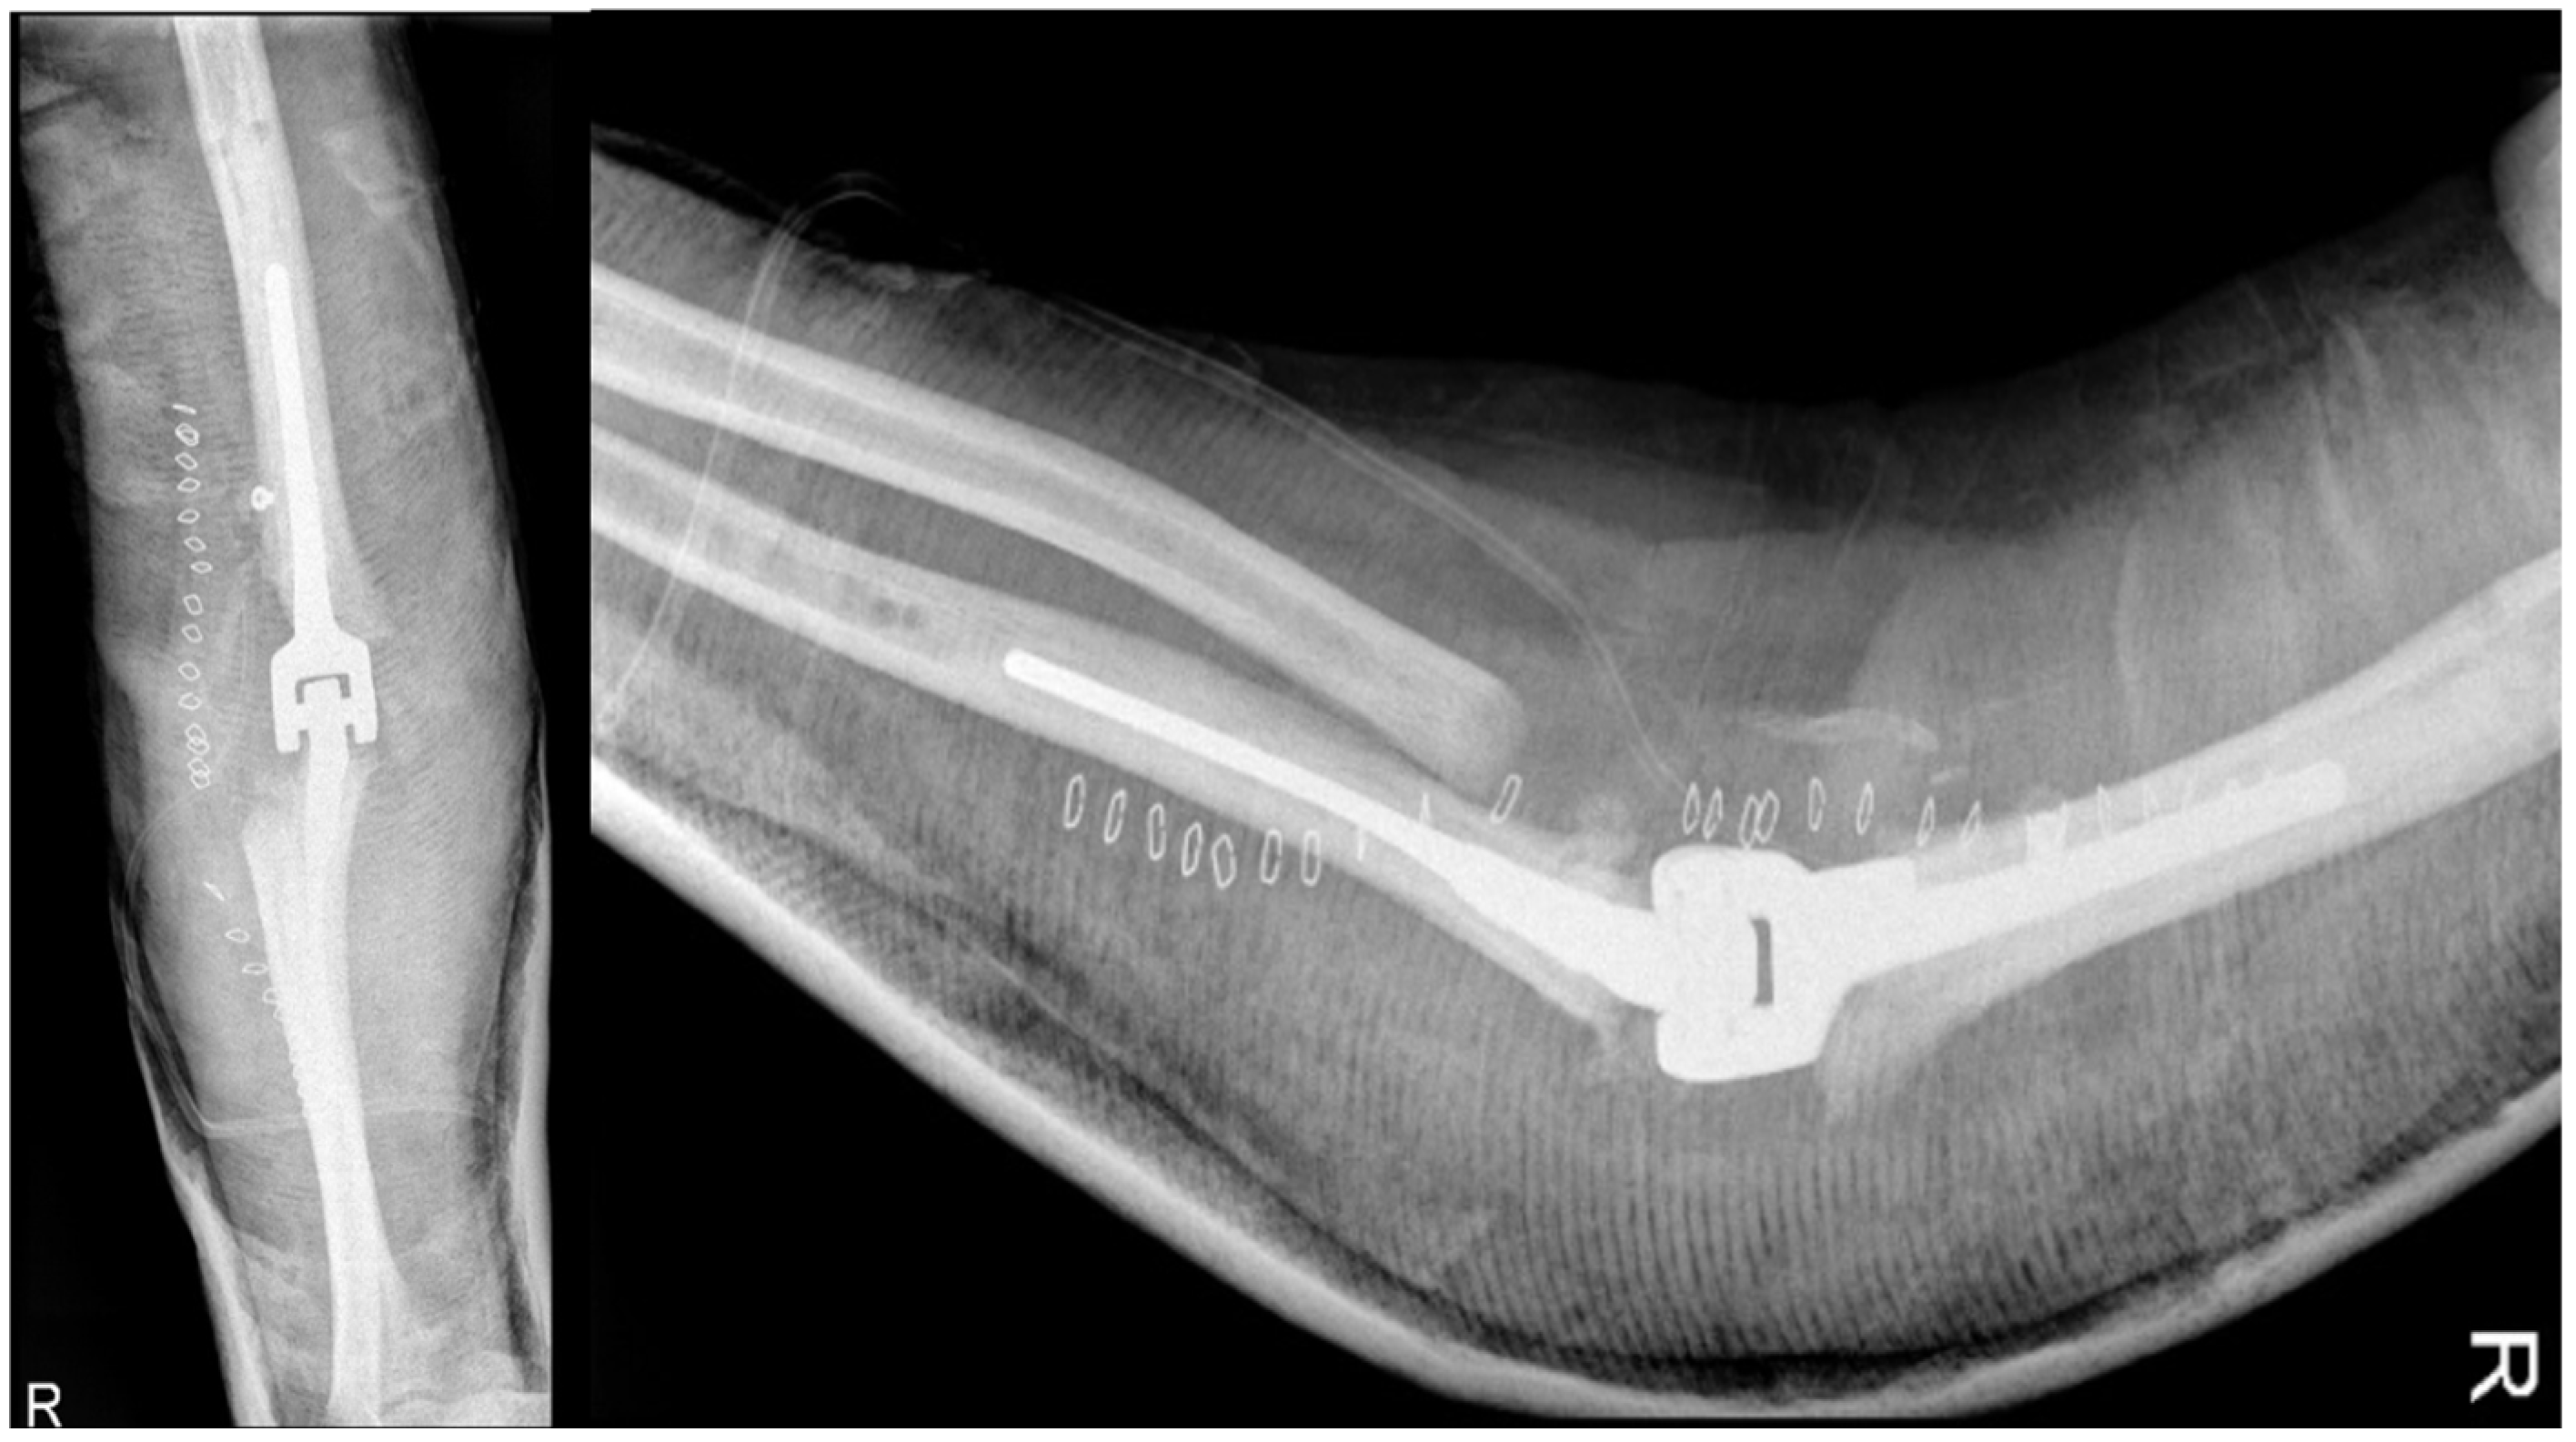

2.4.6. Revision Total Elbow Arthroplasty

- Evidence from the Scientific Literature